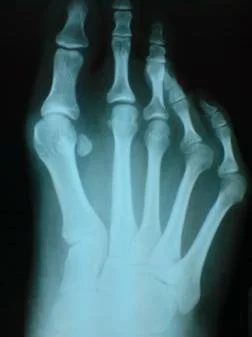

Hallux Valgus

Hallux valgus. Caso clínico:

Paciente femenino de 32 años de edad, quien consulto por dolor en pie derecho, secundario a hallux valgus por metatarso primo varo. Fue intervenida quirúrgicamente con excelentes resultados. Ver más.